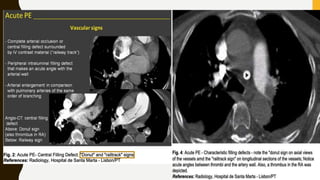

• CT pulmonary angiography (CTPA) will show filling defects

within the pulmonary vasculature with acute pulmonary emboli.

• When the artery is viewed in its axial plane the central filling

defect from the thrombus is surrounded by a thin rim of

contrast, which has been called the Polo Mint sign.

IMAGING

• Chronic thromboemboli are often complete occlusions or

non-occlusive filling defects in the periphery of the affected

vessel which form obtuse angles with the vessel wall

• Features noted with chronic PE include:

–Webs or bands, intimal irregularities

–Abrupt narrowing or complete obstruction of the pulmonary

arteries

–“Pouching defect” which are defined as chronic

thromboembolism organized in a concave shape that “points”